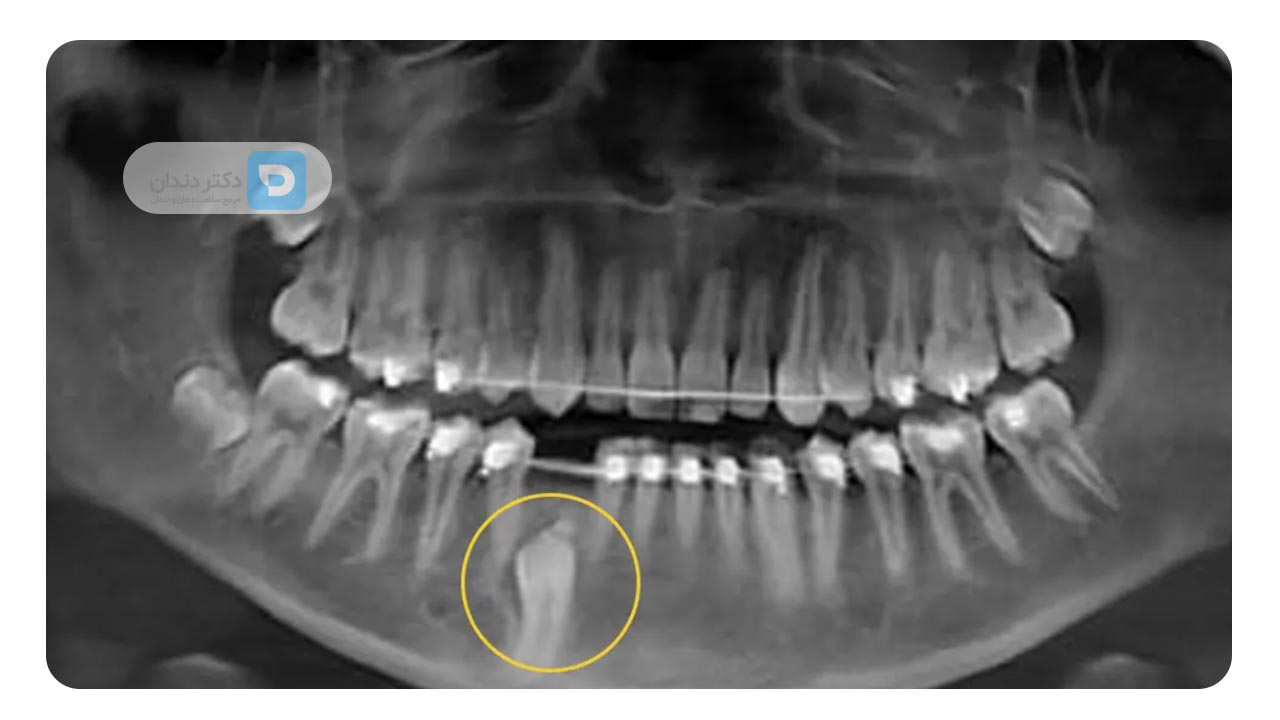

نهفته یا نیمه نهفته بودن دندان ها

گاهی اوقات ممکن است دندان نهفته یا نیمه نهفته باشد. به این یعنی که به طور کامل از خط لثه بیرون نزده باشد. در این حالت ممکن است کشیدن دندان برای جلوگیری از عفونت یا آسیب به دندان های دیگر ضروری باشد. دندان نیش و دندان عقل معمولا بیشترین احتمال را دارد که به صورت نهفته و نیمه نهفته باشند. در بیشتر موارد، کشیدن دندان برای ارتودنسی پیرامون نهفته بودن این دو نوع دندان است.

در اغلب موارد، دندان هایی که برای ارتودنسی کشیده می شوند، آسیای کوچک (پری مولرها) هستند؛ چون با کشیدن آن ها می توان فضای لازم برای جابهجایی بقیه دندان ها را ایجاد کرد، بدون اینکه به ظاهر لبخند یا عملکرد جویدن آسیبی وارد شود. البته بسته به شرایط هر فرد، گاهی نیاز به کشیدن دندان های دیگر هم وجود دارد. برای مثال، کشیدن دندان نیش برای ارتودنسی زمانی انجام می شود که نیش در موقعیتی غیرقابل اصلاح قرار داشته باشد. یا در بعضی بیماران بزرگسال، کشیدن دندان عقل برای ارتودنسی به منظور جلوگیری از شلوغی دندان ها توصیه می شود. در کودکان نیز گاهی کشیدن دندان شیری برای ارتودنسی انجام می شود تا مسیر رویش دندان های دائمی هموار شود. در هر صورت، کشیدن دندان سالم برای ارتودنسی فقط زمانی انجام می شود که ضروری باشد و با تشخیص دقیق متخصص صورت گیرد.